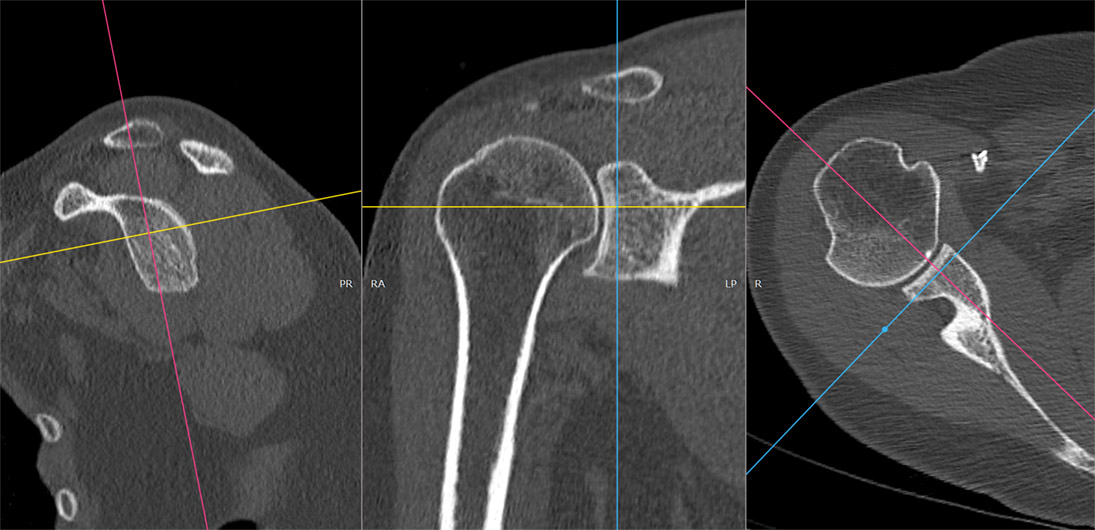

Introducerea tehnicii de achiziție spirală, care a permis achiziția continuă și rapidă a unui volum de date uriaș, cu posibilitatea de reconstrucție ulterioară în orice plan, nu doar cel transversal, precum și cu posibilitatea de reconstrucții tridimensionale spectaculoase. Inițial, achiziția se făcea doar în modul secvențial: după o rotație de 360 de grade a tubului, masa cu pacientul avansa în interiorulul aparatului cu grosimea unui slice (de obicei 10mm) și se făcea o noua achiziție. Acest mod este mai lent și nu permite reconstrucții în alt plan la fel de ușor ca achiziția spirală, la care tubul se învârte continuu, iar masa se mișca și ea în același timp. În prezent, achiziția secvențială se mai utilizează de rutină numai la examinarea cerebrală.

Algoritmii de reconstrucție sunt din ce în ce mai buni, putând reprezenta tot mai exact anatomia internă a corpului, cu iradiere din ce în ce mai mică. Reconstrucțiile tridimensionale devin mai exacte decât atlasele de anatomie și în felul acesta un extraordinar material didactic pentru studenți și rezidenți.